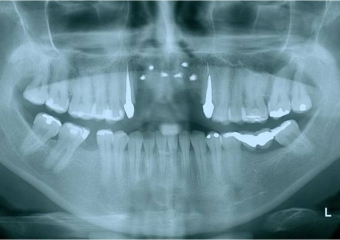

Raio x final